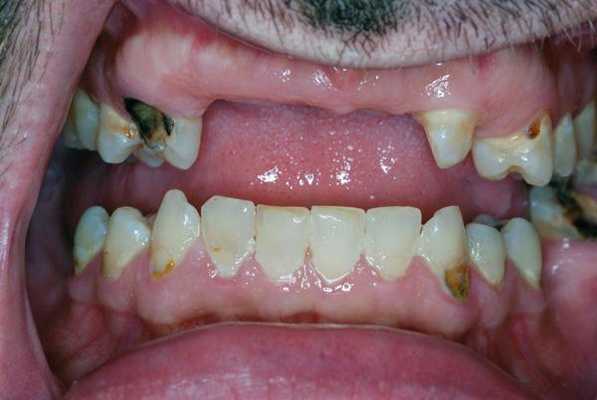

При уменьшенном слюноотделении слизистая оболочка полости рта становиться сухой и в ходе диагностике к ней могут прилипать перчатки, валики и даже стоматологические зеркала. На спине языка могут визуализироваться нитевидные сосочки и трещины, наличие которых позволяет поставить диагноз волосатого языка (фото 1). В пришеечных областях зуба часто визуализируются участки кариозного поражения (фото 2), небольшие эритематозные пятна диагностируются на слизистой щеки, где также могут присутствовать следы накусывания от зубов (фото 3). У пациентов также могут отмечаться признаки гингивита, рецессии и пародонтита (фото 4).

Фото 2. Кариозные и сопутствующие поражения у пациента с ксеростомией.

Также при ксеростомии возникают новые и рецидивируют существующие участки кариозного поражения, при этом пожилые пациенты являются наиболее уязвимыми к подобным осложнениям, поскольку большее количество их собственных зубов уже подвергалось стоматологическому лечению, а в пришеечной области таковых часто наблюдаются участки рецессии десен. Особенно часто рецессии возникают со щечной поверхности ранее восстановленных фронтальных зубов (фото 1).

Фото 1. Вид полости рта пациента с острыми кариозными поражениями вестибулярных и пришеечных поверхностей зубов, вызванные долгосрочным приемом антихолинергических препаратов.